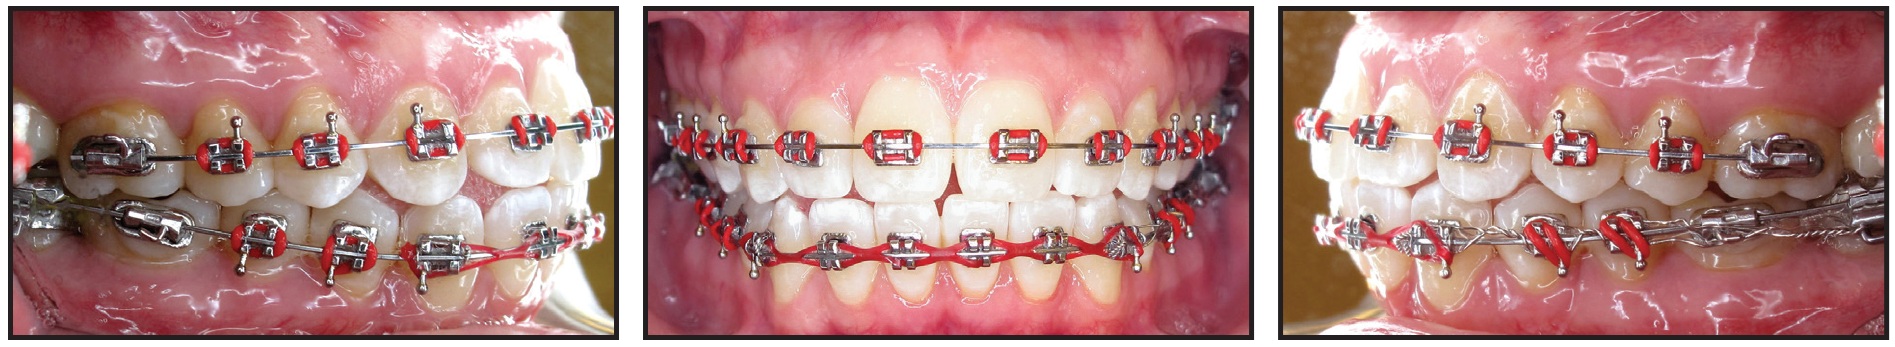

Total treatment time was 21 months (Fig. 10A). A normal overbite and overjet were established, while the Class I occlusion was maintained. The midlines were coincident, and a straighter profile was achieved. The patient showed slightly increased incisal angulations, proper root angulations, and normalized condylar positions with no further condylar remodeling. Cephalometric superimpositions indicated flaring of the upper and lower incisors and some mandibular protrusion (Fig. 10B).

Fig. 10 A. Patient after 21 months of treatment (continued in next image).

Fig. 10 (cont.) B. Superimposition of pre- and post-treatment cephalometric tracings.

A lower 3-3 retainer was bonded. Upper and lower Essix*** retainers were prescribed to be worn 24 hours per day (except while eating) for three months, after which the patient could switch to nightly wear. She reported no post-treatment TMD symptoms.